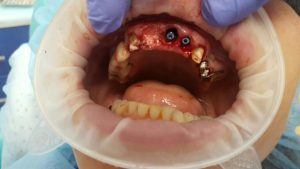

A patient case to the dental clinic with complaint connected with frond teeth defects. After the examination, he decided to provide dental treatment that includes immediate implantation of Alpha Dent implants. During the surgery he has placed 3 Alpha Dent implants in extracted teeth alveolar sockets. Then he placed allomaterial for bone regeneration over implants and sutured the wound.